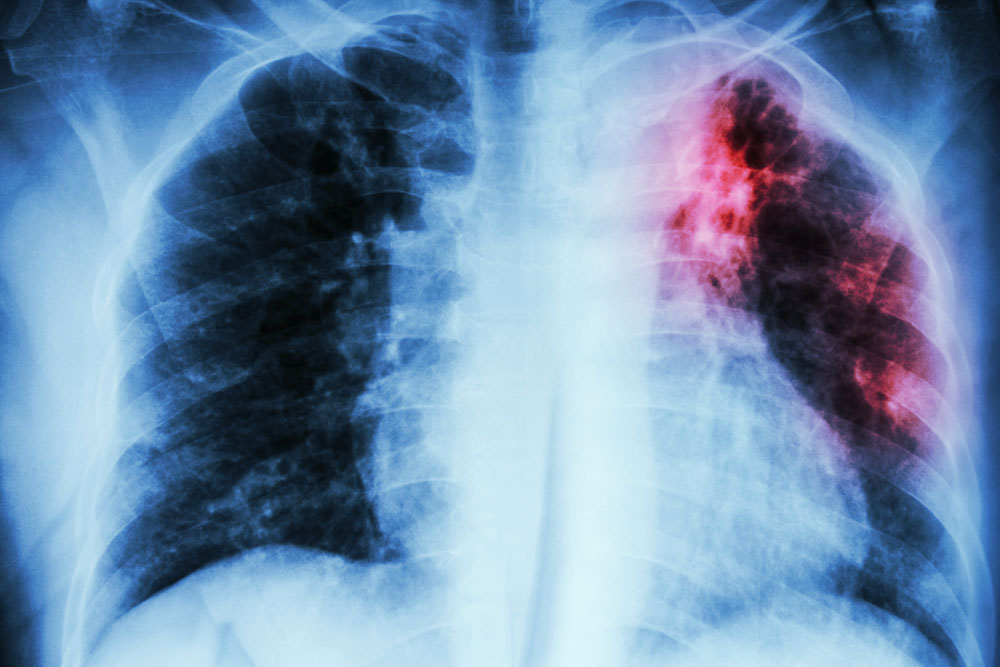

- Imaging test

If the person has had a positive skin test, the doctors will likely order a chest x-ray and CT scan. The white spots in the lungs show active spots of tuberculosis. - Blood tests